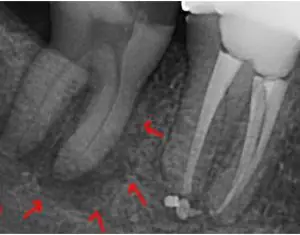

A patient came in with pain in tooth No. 18. It had a history of a small crack that resulted in needing a root canal.